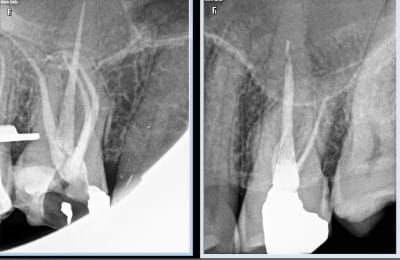

Comparaison des traitements de 2 praticiens différents au même tarif. Même patient 16 26. Pourquoi se faire chier aucun souci sur 26. ,

> Comparaison des traitements de 2 praticiens différents au même tarif. Même

> patient 16 26. Pourquoi se faire chier aucun souci sur 26. ,

> c est terrible parce que selon Gabzou... le gars qui a foiré l endo 26 a fait

> exprès puisque c est facile...

Indépendamment du reste, il y a clairement une racine MV non traitée dont on distingue le canal, ce qui est l'anatomie standard d'une 26.

Conclusion, le praticien l'a sciemment ignorée pour aller plus vite.

On peut discuter de la rémunération, des raisons qui ont amené ce praticien à choisir de bâcler le travail, mais il est indiscutable que le praticien ne peut pas avoir ignoré avoir fait n'importe quoi.

J'ai bien précisé que tout n'est pas facile. Cette 26 l'est, je n'ai quasiment aucun doute.